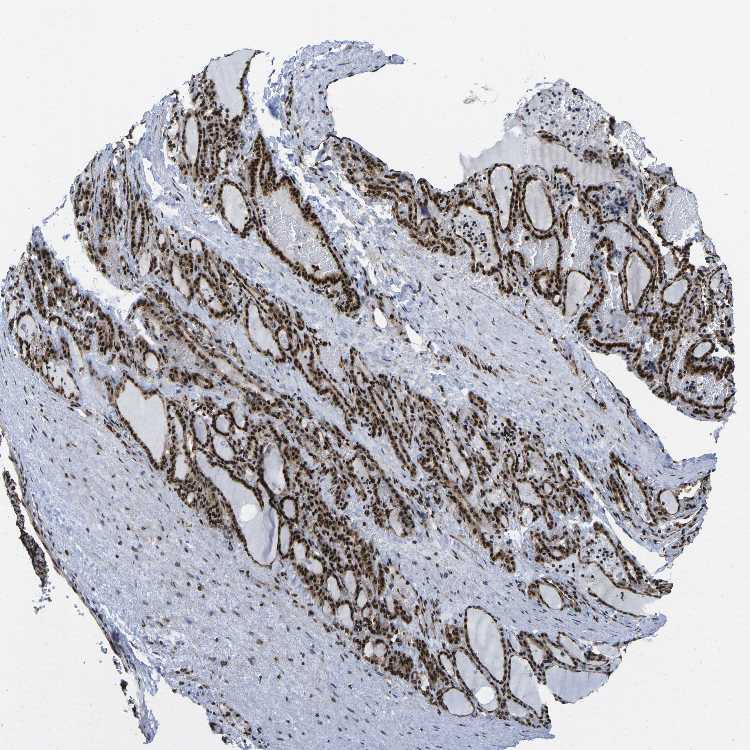

POLR2A